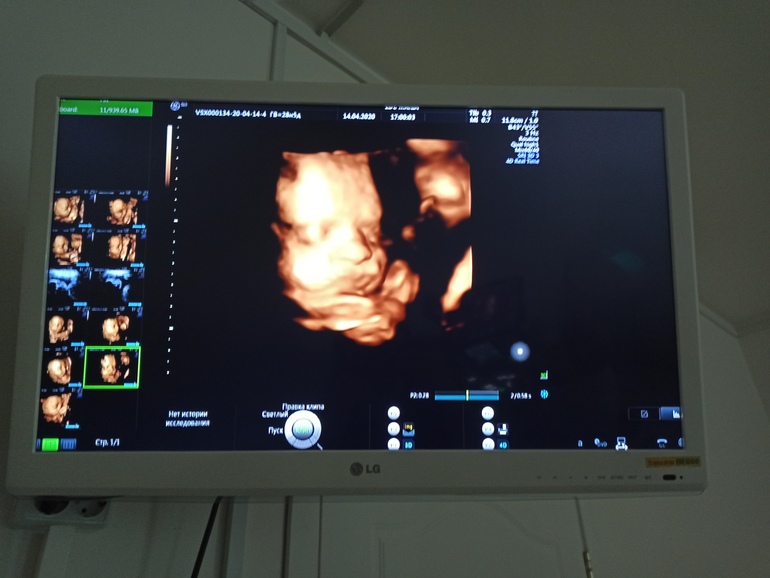

7 мая будет

третий скрининг, что-то волнительно) Это фото с 3Д УЗИ в 28 недель.